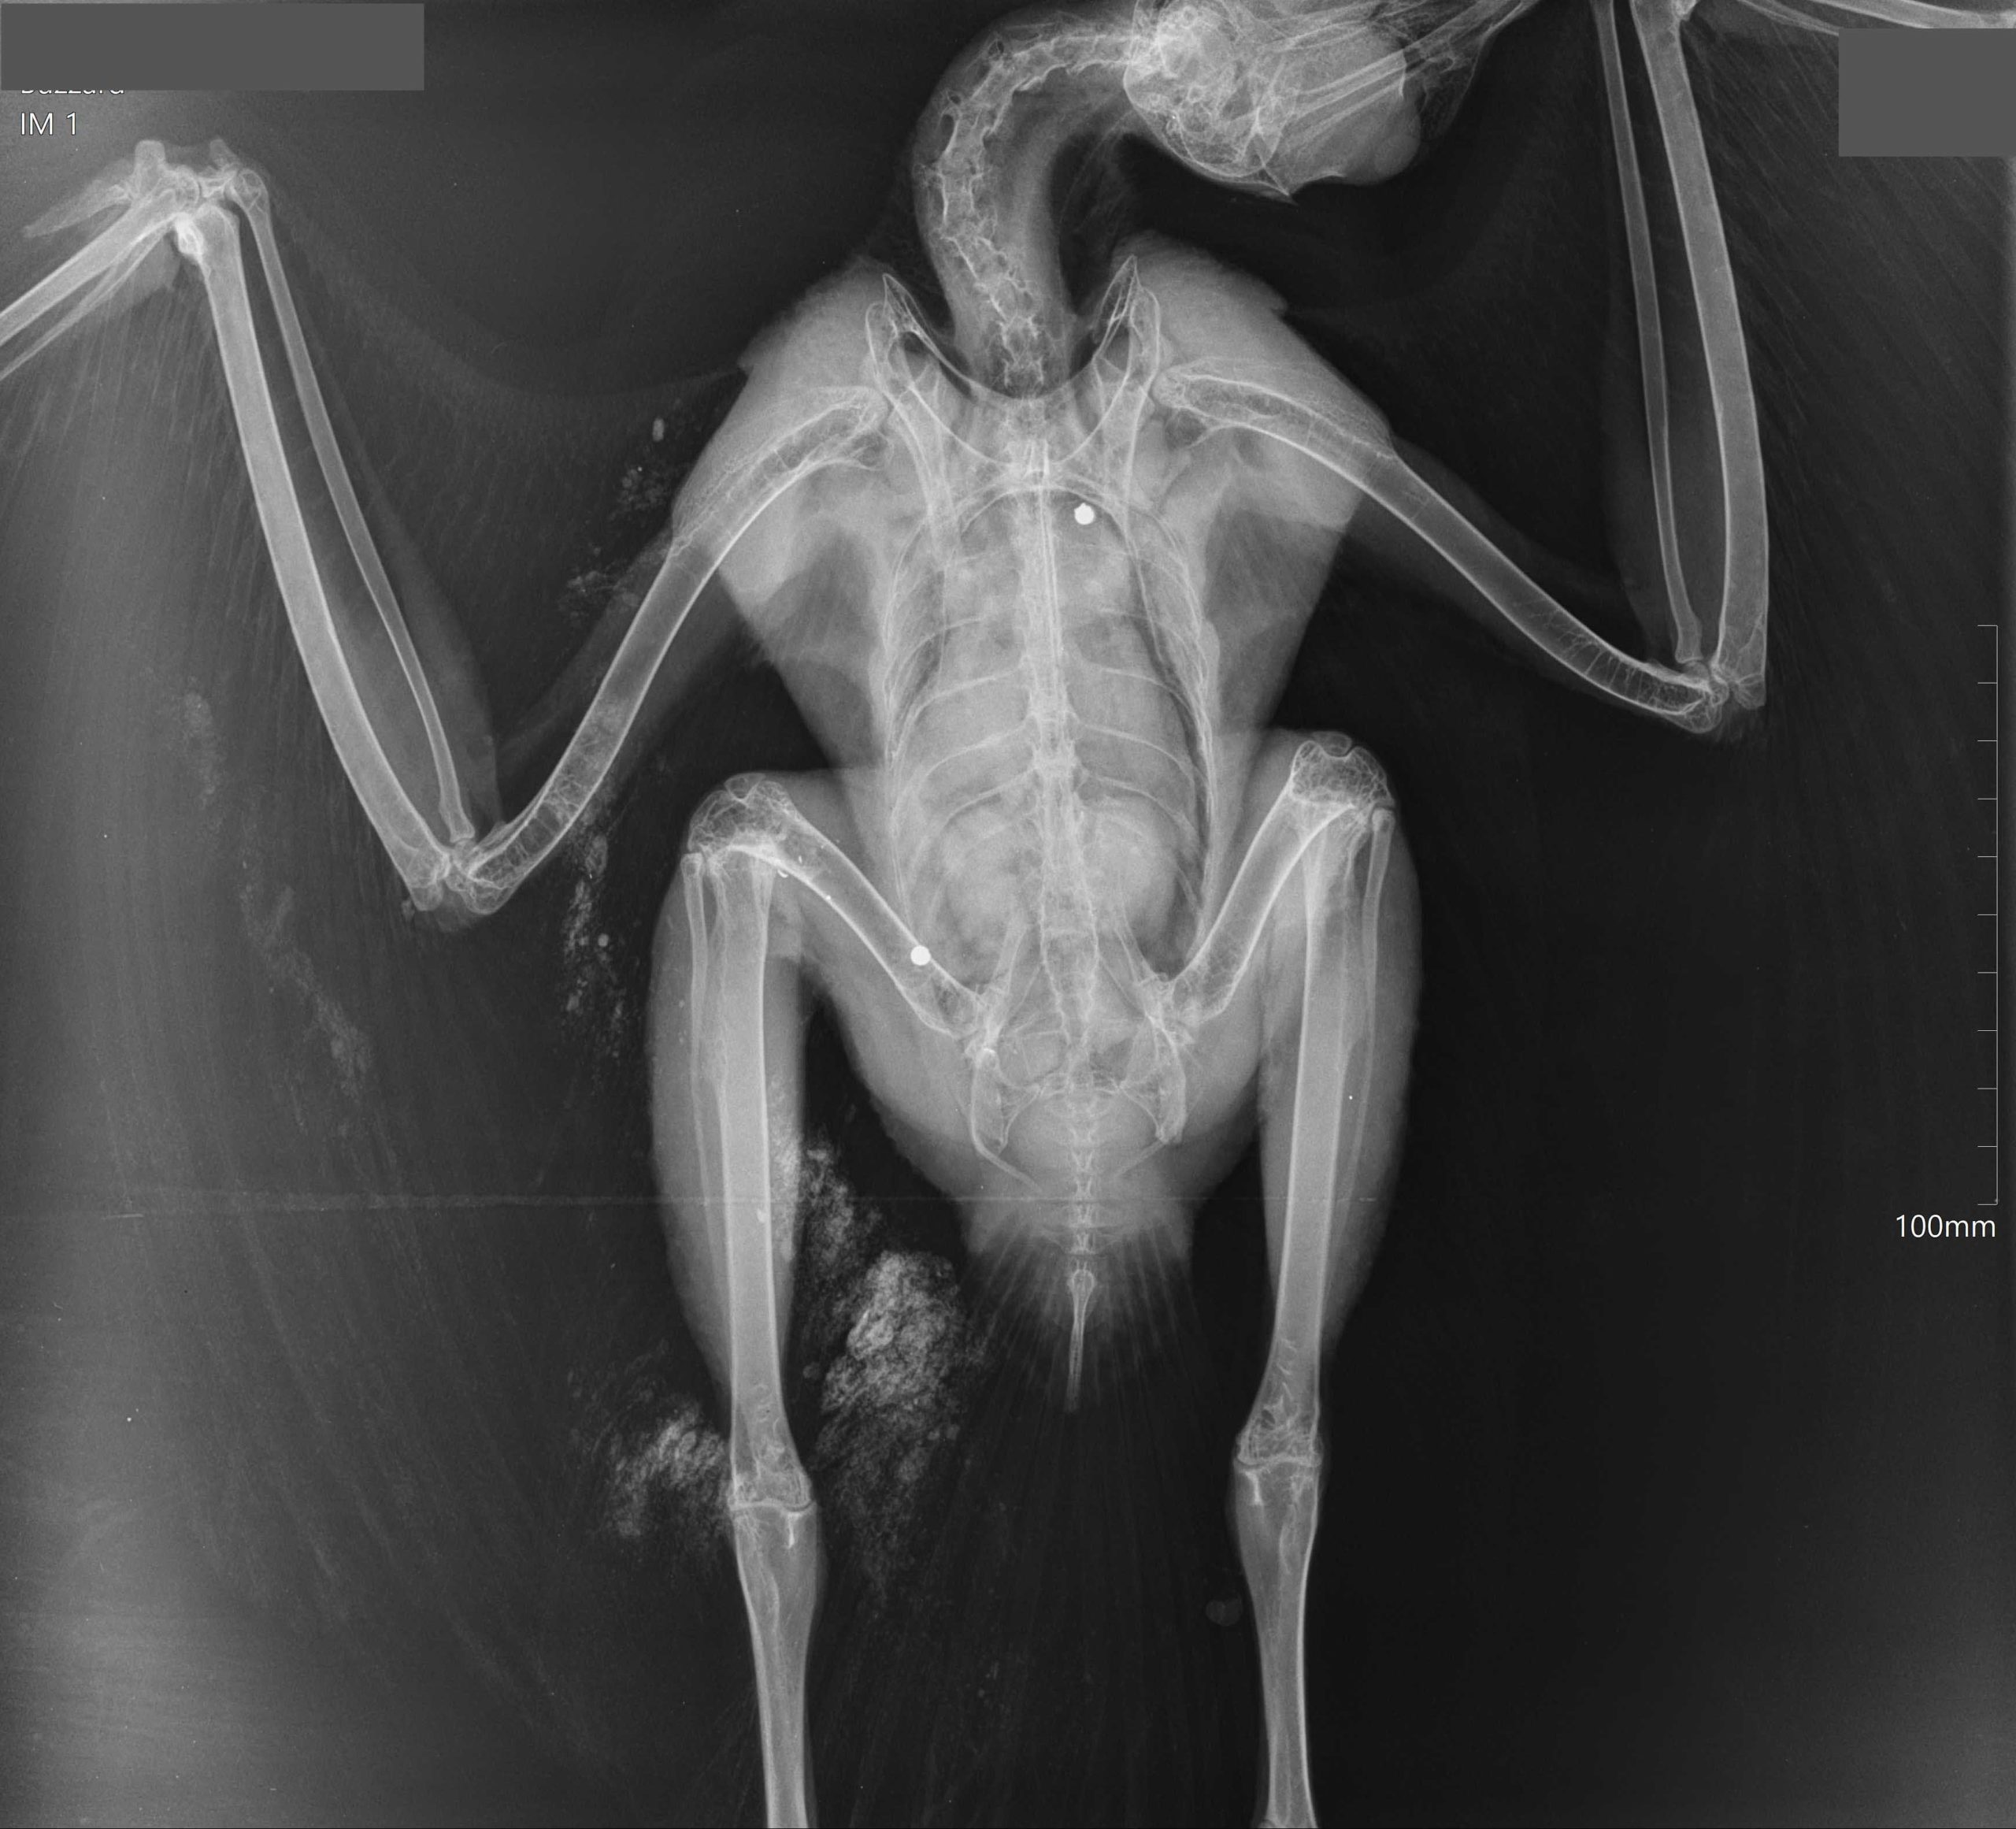

[This male hen harrier died in 2019 after his leg was almost severed in an illegally set trap that had been placed next to his nest on a Scottish grouse moor (see here). Photo by Ruth Tingay]

11 May 2019: An untagged male hen harrier was caught in an illegally-set trap next to his nest on a grouse moor in South Lanarkshire. He didn’t survive (here)